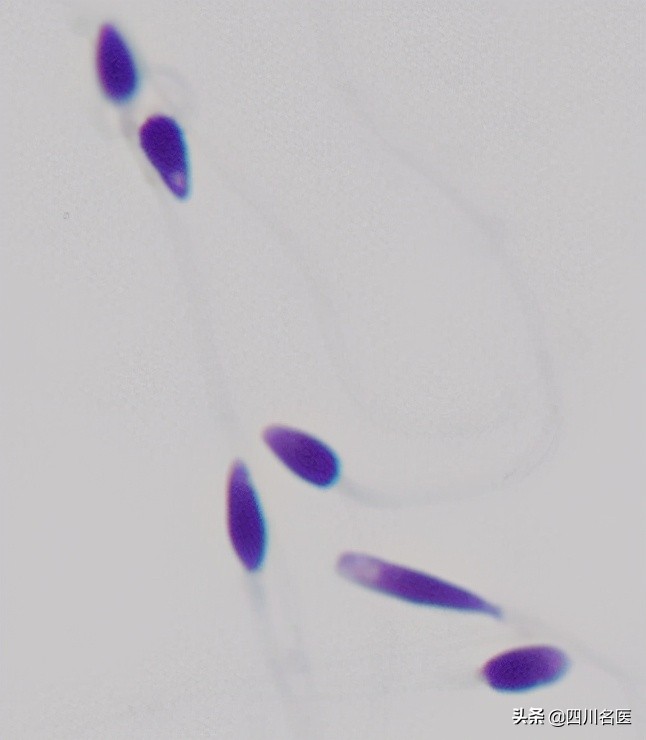

首先,让我们请出本届大赏冠军获得者、精子中的“美人”标杆↓

▲正常形态的精子, 头部大体呈椭圆形,还有一顶“帽子” (顶体)。

常见的头部畸形精子

大概有这些↓

精子的形态

是精液实验室分析的一个重要指标

通常情况下

只有形态正常的精子

才能完成受精